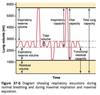

What lowers aspiration events

Increase in cricoid pressure

Rapid intubation

Use of rapid acting and paralytic meds

Subglottic suctioning